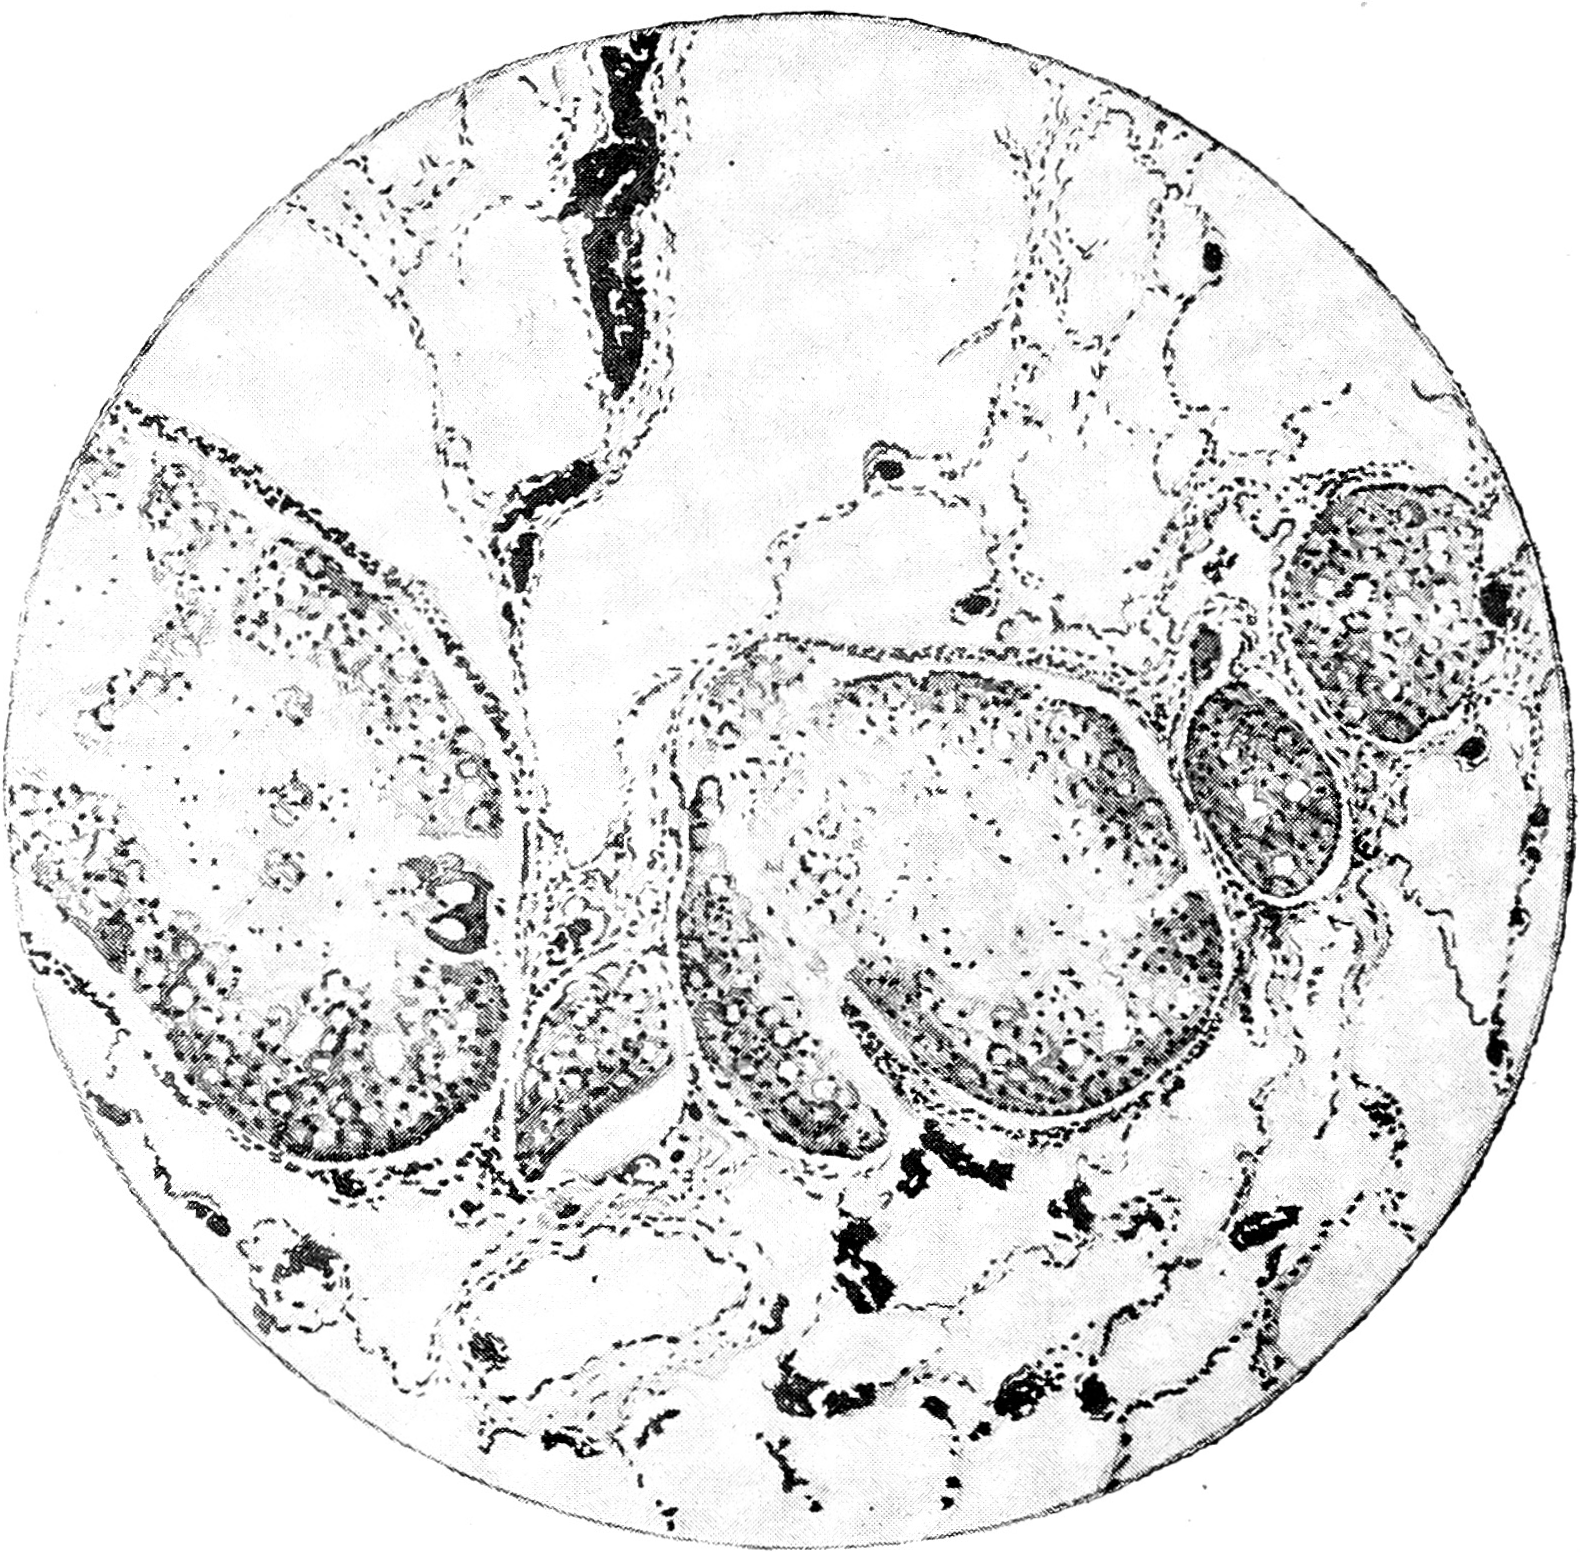

Новообразование с висцеральной плевры внедрялось по интерстициальным междольковым прослойкам вглубь легкого. Эти интерстиции так же, как и плевральный листок, были утолщены и образованы плотной соединительной тканью. Очаги опухоли имели альвеолярное строение с резко выраженною склонностью клеток к слизистому перерождению. Здесь ясно было выявлено стремление клеток опухоли распространяться по существующим лимфатическим путям (рис. 2) и проникать до бронхов и больших сосудов. Перехода новообразования на межальвеолярные перегородки и внутрь альвеол не обнаружено.

Рис. 2

Рис. 2. Раковые гнезда в лимфатических сосудах интерстициальных прослоек легкого. Пустоты среди клеток новообразования и светлые центральные части гнезд—очаги слизи. Leitz, Ob. 3, Ок. 4.